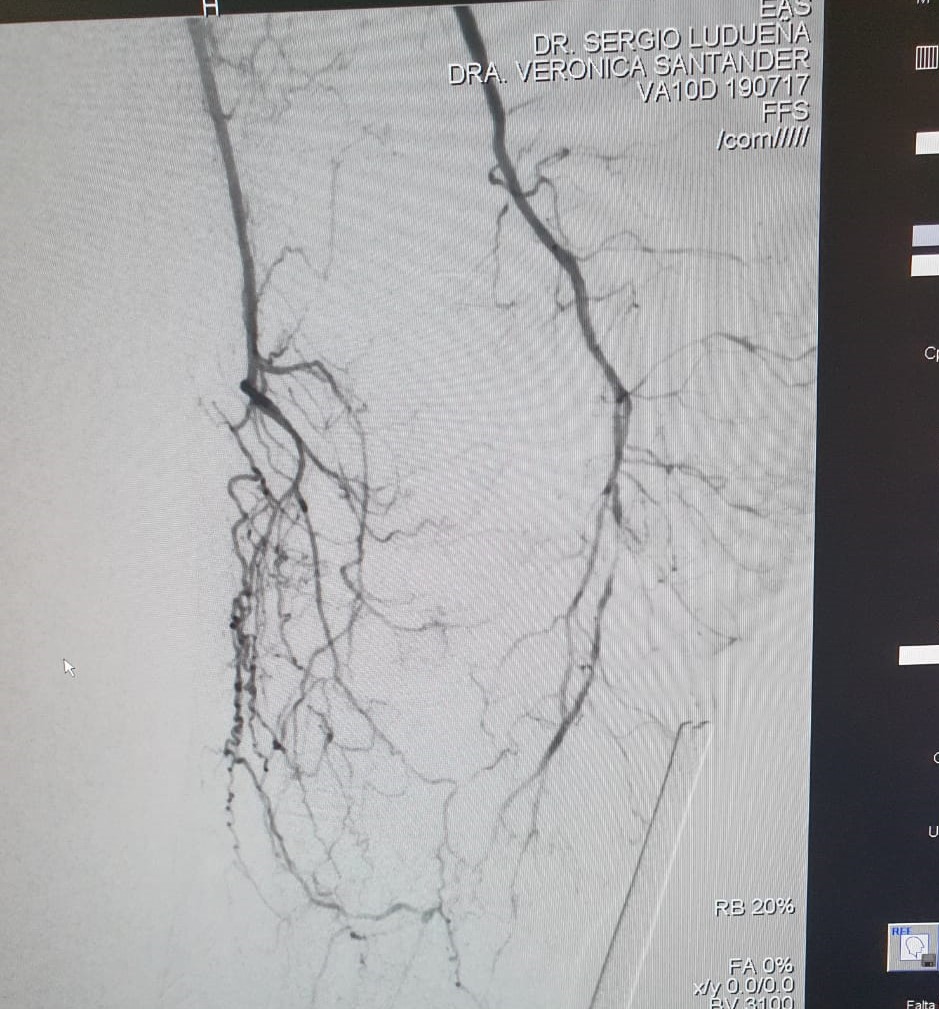

El Dr Sergio Raul Ludueña Jefe del Servicio de Hemodinamia de INCOR nos comentó sobre procedimiento realizado en el día de ayer en en el Servicio. "Queremos compartir con ustedes si bien no es un caso coronario , es un paciente obeso mórbido, diabético, con amputación supracondilea de miembro inferior izquierdo hace 3 años y actualmente con isquemia critica de miembro inferior derecho, con oclusión de ambas tíbiales y sin circulación en el pie".

Se realizó un abordaje híbrido con el Dr. Alejandro Flores, y se re canalizó ambas arterias tíbiales. Procedimiento inédito en nuestra provincia.

Las imágenes siguientes son previas al procedimiento y posterior se ve ambas arterias tíbiales permeables, y circulación en el pie